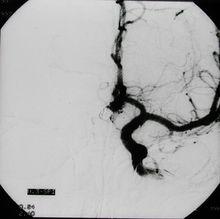

腦栓塞

相關書籍N-BCA是一種低粘度的液體,一旦與血液的電解環境接觸就立即發生聚合。將n-BCA稀釋到油性的碘造影劑(如碘化油或乙碘油)中可以延緩聚合時間,或者將其酸化也可達到類似目的。這樣做是為了使這種膠狀物體能夠在發生聚合之前到達注射部位遠端的靶位點。根據病變位置和血流速度不同,為了增加乳化效應和粘度,通常還需加入鉭粉末。儘管已經被大量套用於硬膜動靜脈畸形的栓塞,但是n-BCA較少用於顱外腫瘤的栓塞。它的使用必須嚴格監測以防通過吻合支或是直接進入到其它區域,引起重要組織的缺血或壞死。同時需要相當的技巧來防止膠粘在導管的頭端。